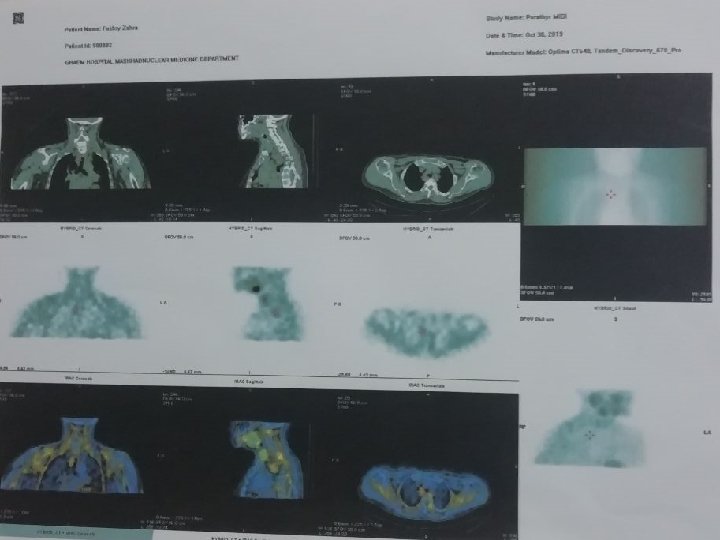

Parathyroid scan and SPECT/CT 98/8/8